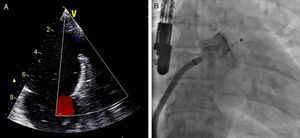

Sob sedação profunda/anestesia, efetuou-se o ecocardiograma transesofágico, realizado aos 0°, 45°, 90° e 135°, para excluir novamente a presença de trombos no AAE, medir a profundidade e o maior diâmetro do ostium (Figura 3).

Foi efetuada punção transeptal, sob controlo fluoroscópico e ecocardiografia transesofágica, e colocado guia superstiff, através do qual foi avançado um cateter multipurpose até ao AAE. De seguida, foram efetuadas 2 injeções de contraste (RAO 20° caudal 20°, RAO 20° cranial 20°) com preenchimento do AAE (Figura 3) para sua medição.

Os dispositivos foram colocados no AAE, seguindo-se uma avaliação ecocardiográfica e fluoroscópica do seu posicionamento e fixação.

Considerou-se que o ACP estava bem posicionado quando 2/3 do lobo se encontravam distais à artéria circunflexa por ecocardiograma transesofágico, e assumia uma conformação que traduzisse alguma compressão do lobo pelo AAE. Foi ainda avaliada a presença de fluxo peridispositivo, considerando-se critério de sucesso a ausência de blush significativo por fluoroscopia, e um fluxo peridispositivo < 3mm (ligeiro) por ecocardiograma transesofágico, com base na classificação proposta por Ostermayer e et al26.

Após se satisfazerem todos estes critérios de bom posicionamento, o dispositivo foi libertado e realizou-se nova avaliação fluoroscópica e ecocardiográfica (Figura 4) para avaliar eventuais complicações imediatas, como deslocamento ou migração do dispositivo, formação de trombo intracardíaco ou adjacente ao dispositivo, derrame pericárdico, compressão da artéria circunflexa ou da veia pulmonar superior esquerda, ou a presença de fluxo residual. No caso de estes critérios não se encontrarem satisfeitos, o dispositivo deveria ser total ou parcialmente recapturado e reposicionado antes de ser libertado.